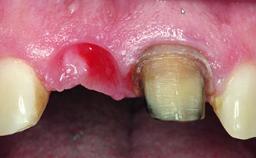

Replacement of a Failing Restored Upper Right Central Incisor, Ridge Preservation and Early Placement of an RC Bone Level Implant

A 23-year-old female, healthy and non-smoking patient had had tooth 11 temporarily restored following a trauma in adolescence. As the patient’s growth had since come to an end and the crown had fractured, she requested an implant-supported restoration of tooth 11. Moreover, the contralateral tooth 21 presented an old composite restoration at the mesial incisal edge. The periodontal tissues were healthy with periodontal probing depth values below 3 mm, but some inflammation was observed around the semi-submerged root of tooth 11.